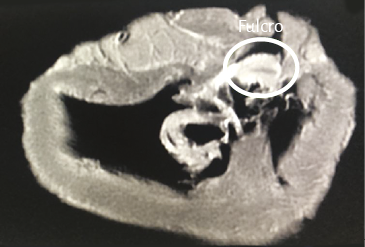

Al inicio del desplegamiento miocárdico lo primero que se interrumpe es un núcleo condroide, donde confluyen ambos extremos del miocardio y al cual hemos denominado fulcro cardíaco (211). Discontinuado este punto, se divorcian los extremos del miocardio. El segmento derecho (inicio) se amarra fundamentalmente a la superficie anterior del fulcro. El segmento ascendente, extremo final del miocardio, ingresa al fulcro fundamentalmente por la parte inferior (figuras 18, 21, 33 y 51). En esta maniobra el miocardio pierde la integridad. Desaparece su solidez integral. El sector del segmento derecho que se extiende desde el fulcro hasta la arteria pulmonar es el tronco pulmotricuspídeo simplemente adosado al segmento ascendente ubicado posteriormente (figuras 29 y 30).

Análisis histológico del fulcro cardíaco. En las investigaciones anatómicas hemos hallado en todos los corazones de bóvidos y de humanos un núcleo cuya estructura histológica es diferente de acuerdo con los especímenes analizados, presentándose como de carácter óseo, condroide o tendinoso. En esta estructura se amarran tanto las fibras musculares del segmento derecho (inserción inicial) como las del segmento ascendente (inserción final). Durante la disección del miocardio, el hallazgo en esta investigación del fulcro cardíaco como núcleo donde se inserta el miocardio nos condujo a otras indagaciones: ¿cuáles eran sus características?, ¿qué ubicación ostenta?, ¿cuál es la histología?, ¿es análoga su presencia en distintas especies?, ¿cómo se inserta el músculo miocárdico en dicha estructura que hemos denominado fulcro cardíaco?

La existencia de una formación ósea, denominada os cordis, en bóvidos y ovejas es un hecho mencionado en ciencia veterinaria. Con posterioridad a nuestra primera publicación en 2018 sobre su hallazgo en el hombre (205), últimamente también fue ubicado en el chimpancé (109). En estas referencias es situada en el mismo sitio en el que nosotros hemos investigado esta estructura, tanto en bóvidos como humanos. Más allá de su mera alusión, hasta nuestras investigaciones nunca se le asignó ninguna función ni el sentido de su presencia, como asimismo careció de descripción en el ser humano (figuras 32 y 33) (216).

En bóvidos, la consistencia del fulcro cardíaco, óseo a la palpación (figuras 34 y 35), ha sido confirmada por la histología (figuras 36 a 38). Su tamaño, corroborado por disección (figura 39) y tomografía computada (figuras 58 y 59), es de aproximadamente 37 a 45 × 15 mm y de forma triangular. El análisis microscópico del fulcro cardíaco bovino muestra una matriz osteocondral trabecular con líneas segmentarias. Su estructura general asemeja al crecimiento metafisario de los huesos largos. A mayor aumento se pueden observar trabéculas óseas con osteoblastos y líneas segmentarias secundarias a aposición ósea. Los mismos hallazgos histológicos se han encontrado en chimpancés (109). La inserción secuencial de las fibras miocárdicas en el fulcro bovino se puede observar en las figuras 40-42.